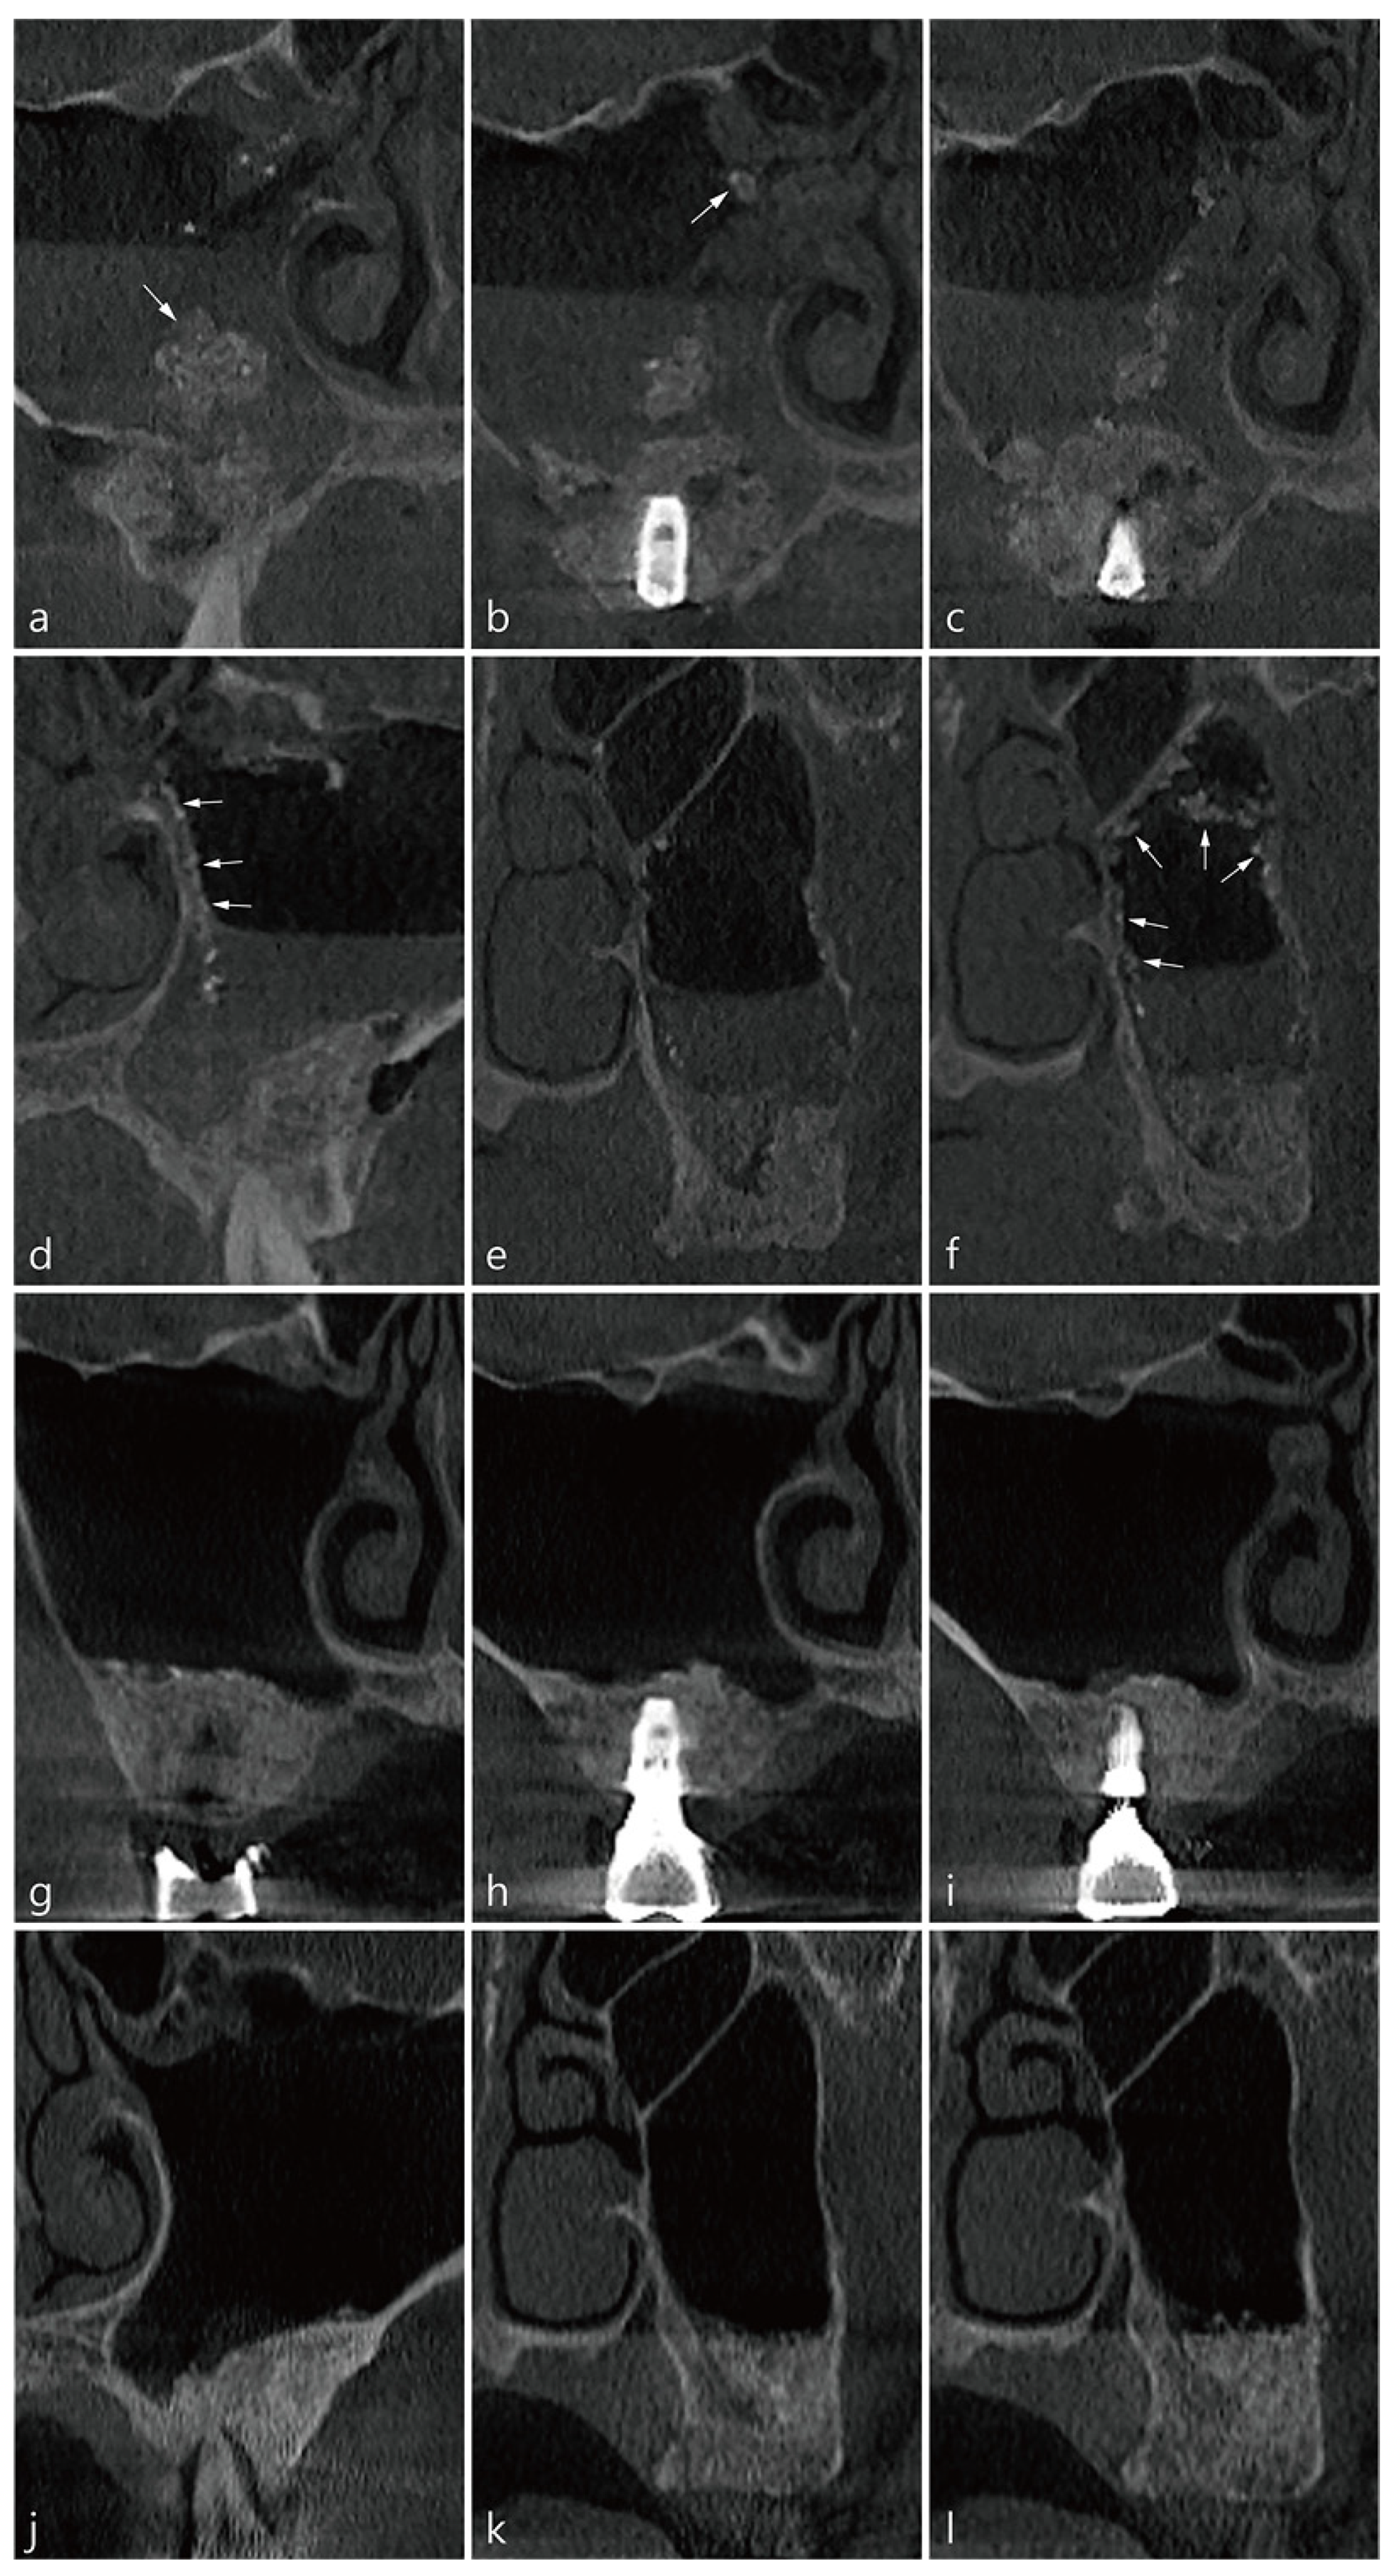

4. Case 2